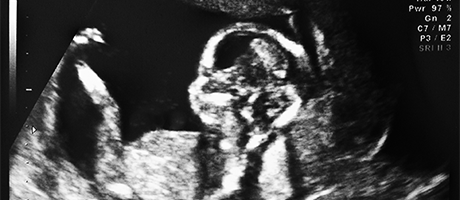

bebé en ultrasonido bebé en ultrasonido Leave a Reply Haz clic aquí para cancelar la respuesta. Name (required) Email (will not be published) (required) Website Comment XHTML: You can use these tags: <a href="" title=""> <abbr title=""> <acronym title=""> <b> <blockquote cite=""> <cite> <code> <del datetime=""> <em> <i> <q cite=""> <s> <strike> <strong>